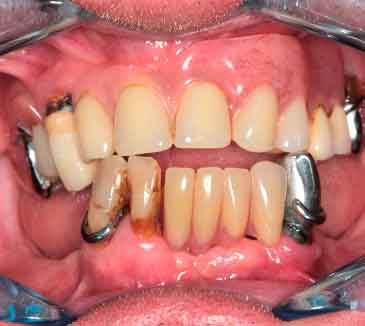

66 years old patient. Wishes to regain functional comfort and improve aesthetics.

Complaints :

- Lack of stability of his removable prosthetics

- Difficulties in eating

- Sagging of the upper lip

The periodontal structures of the remaining teeth are no longer sufficient. An edentulism is considered. The treatment plan is directed towards a removable maxillary complete prosthesis and an implant-supported mandibular complete prosthesis.

Picture - Initial bite situation